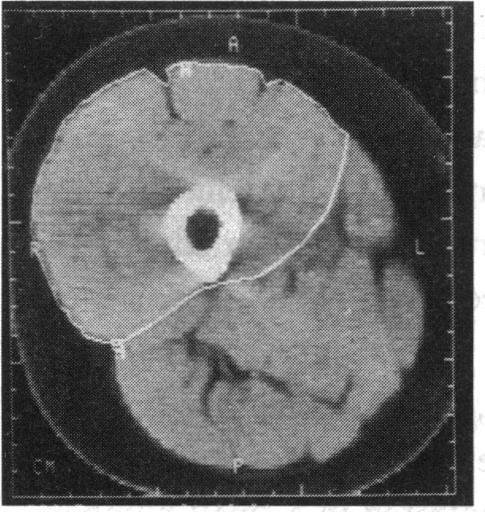

https://cdn.ncbi.nlm.nih.gov/pmc/blobs/7e80/1296173/6afe07a4dd73/jrsocmed00042-0008-b.jpg

https://cdn.ncbi.nlm.nih.gov/pmc/blobs/7e80/1296173/8b6d6dfffa16/jrsocmed00042-0008-a.jpg